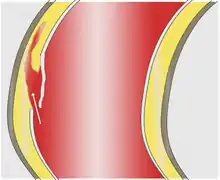

In an aortic dissection, blood penetrates the intima and enters the media layer. The high pressure rips the tissue of the media apart along the laminated plane splitting the inner two-thirds and the outer one-third of the media apart.[26] This can propagate along the length of the aorta for a variable distance forward or backward. Dissections that propagate towards the iliac bifurcation (with the flow of blood) are called anterograde dissections and those that propagate towards the aortic root (opposite of the flow of blood) are called retrograde dissections. The initial tear is usually within 100 mm of the aortic valve, so a retrograde dissection can easily compromise the pericardium leading to a hemopericardium. Anterograde dissections may propagate all the way to the iliac bifurcation of the aorta, rupture the aortic wall, or recanalize into the intravascular lumen leading to a double-barrel aorta. The double-barrel aorta relieves the pressure of blood flow and reduces the risk of rupture. Rupture leads to hemorrhaging into a body cavity, and prognosis depends on the area of rupture. Retroperitoneal and pericardial ruptures are both possible.[27]

The initiating event in aortic dissection is a tear in the intimal lining of the aorta. Due to the high pressures in the aorta, blood enters the media at the point of the tear. The force of the blood entering the media causes the tear to extend. It may extend proximally (closer to the heart) or distally (away from the heart) or both. The blood travels through the media, creating a false lumen (the true lumen is the normal conduit of blood in the aorta). Separating the false lumen from the true lumen is a layer of intimal tissue known as the intimal flap.

The vast majority of aortic dissections originate with an intimal tear in either the ascending aorta (65%), the aortic arch (10%), or just distal to the ligamentum arteriosum in the descending thoracic aorta (20%).

As blood flows down the false lumen, it may cause secondary tears in the intima. Through these secondary tears, the blood can re-enter the true lumen.